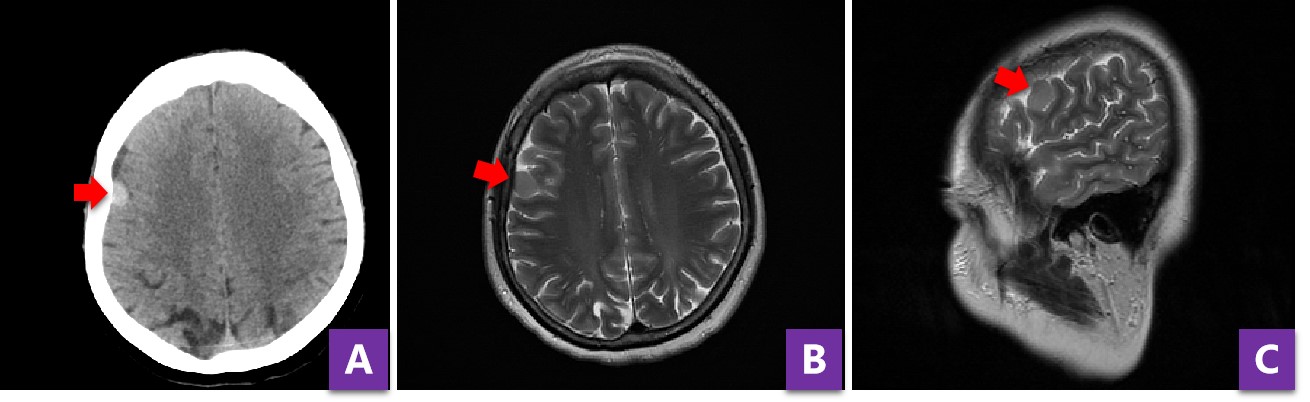

图3 患者增强MRI提示肿瘤均匀强化,起源于硬脑膜

病人目前肿瘤较小,早期开颅手术,不仅创伤小,而且容易根治肿瘤,但缺点是精准定位困难,有了神经导航的辅助,一切困难迎刃而解。在顺利完成肿瘤定位后,手术团队使用显微镜为病人进行肿瘤和病变硬膜的切除。